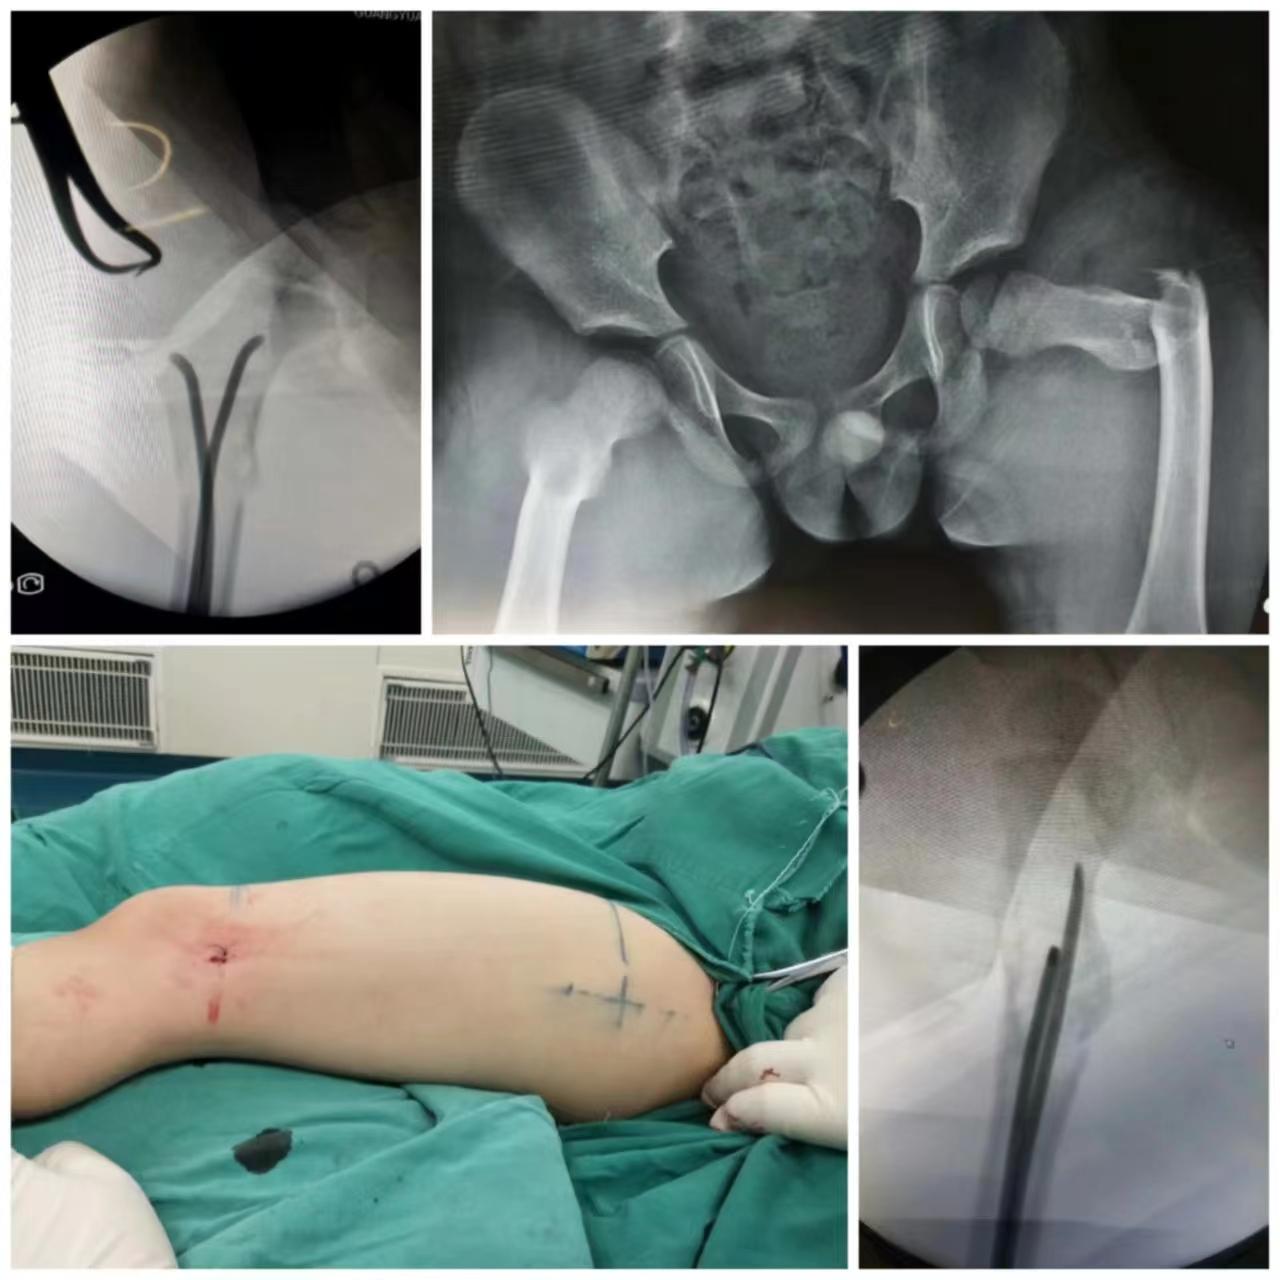

部分病例展示

儿童股骨骨折—微创闭合复位弹性髓内针固定